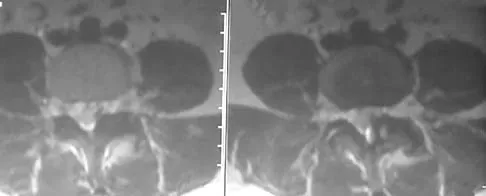

Question 55

The mother of a 3-month-old infant states that she has difficulty positioning the infant's legs during diaper changes. Examination reveals limited abduction of both hips and a negative Ortolani sign. A radiograph reveals bilaterally dislocated hips. Initial management consists of guided reduction in a Pavlik harness, with weekly follow-up. Figures 57a and 57b show the radiograph and CT scan obtained after 6 weeks in the harness. Management should now consist of